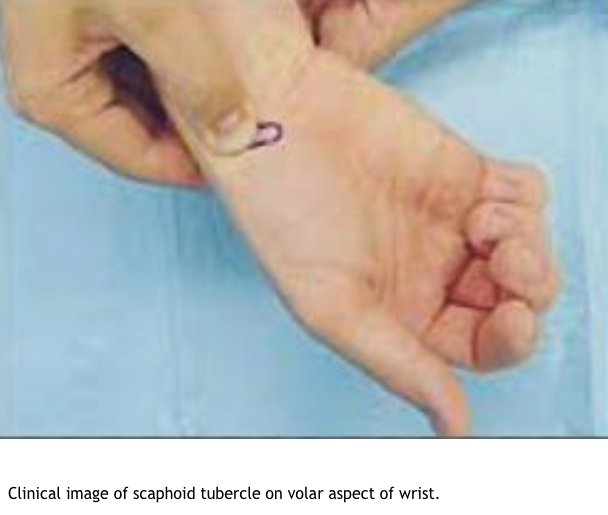

O/E

- Anatomic snuffbox tenderness dorsally

- Scaphoid tubercle tenderness volarly